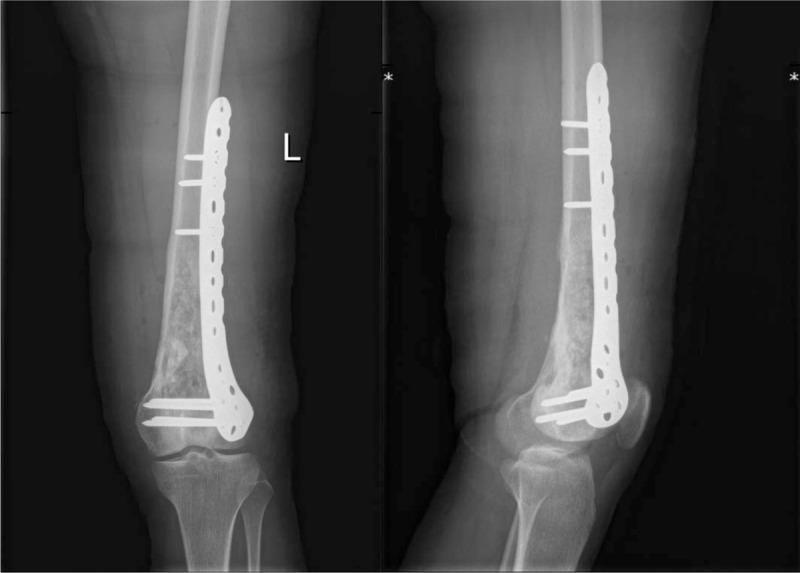

Desmoplastic fibroma of the femur INTERVENTIONS:: Wide surgical resection OUTCOMES:: At the 1-year follow-up visit, no relapse in the tumor was observed.

股骨促结缔组织增生性纤维瘤

干预措施

广泛手术切除

结果

在1年的随访中,未观察到肿瘤复发。